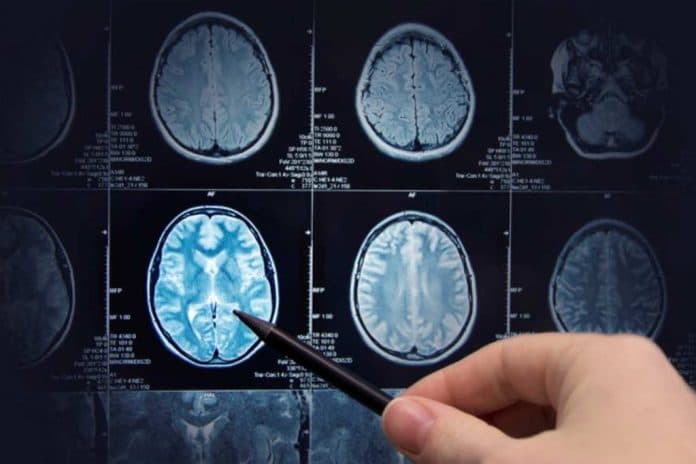

World Health Organization (WHO) merilis hasil penelitian tentang keterkaitan penggunaan ponsel dan risiko kanker otak. Hasilnya menunjukkan bahwa penggunaan ponsel tidak meningkatkan risiko kanker otak.

Studi ini dipimpin oleh Australian Radiation Protection and Nuclear Safety Agency (Arpansa), yang telah meninjau lebih dari 5.000 penelitian. Dari sekian banyak riset, hanya yang paling ilmiah dipilih untuk dianalisis. Sementara yang dinilai lemah dikecualikan.

“Kami menyimpulkan tidak ada bukti ilmiah yang menyebutkan adanya hubungan antara penggunaan ponsel dan kanker otak, ataupun kanker lainnya di area kepala hingga leher,” tambahnya.